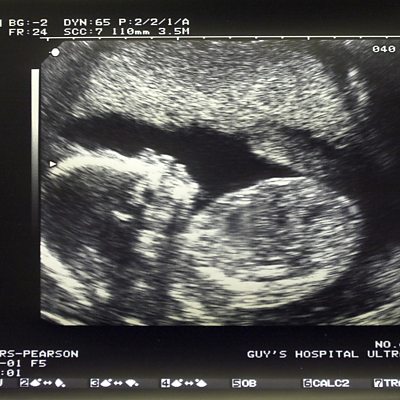

Amanda Benson spoke to Catrin Nye about dealing with Down's Syndrome in surrogacy